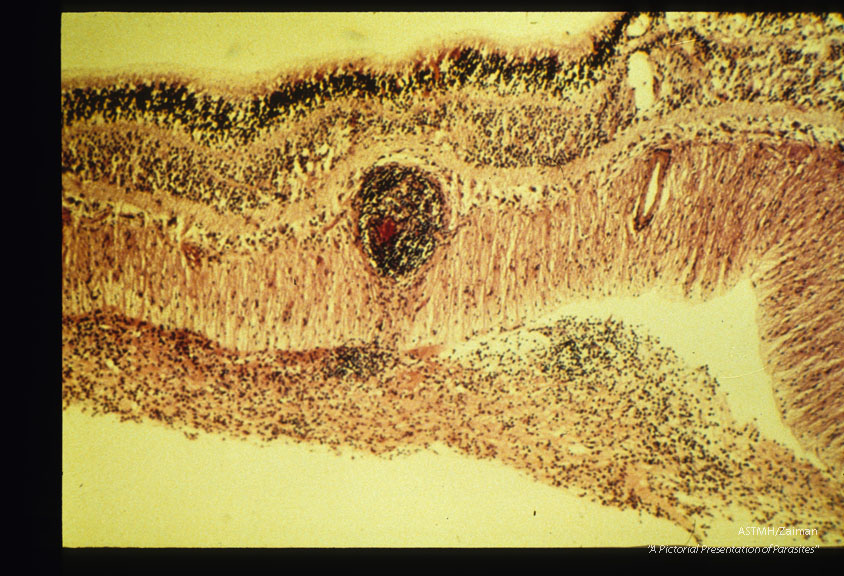

Occular larva migrans. Lymphatic perivascular cuff in human retina.

Toxocara canis

Description: Occular larva migrans. Lymphatic perivascular cuff in human retina.